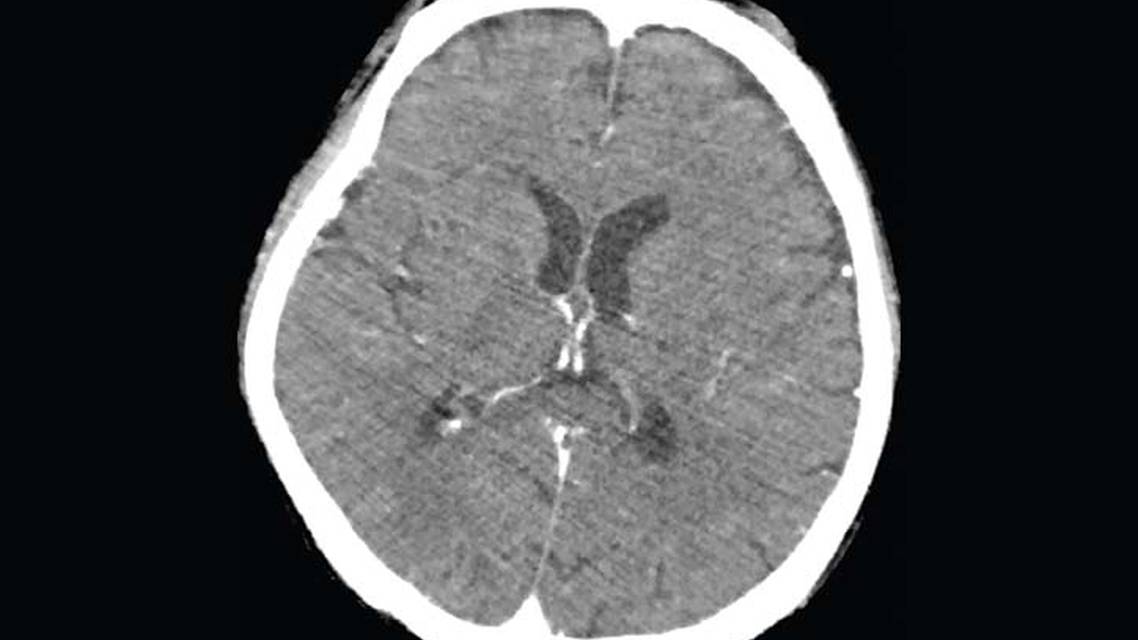

Brain Imaging and Cerebrospinal Fluid Analysis

Head CT with and without contrast were normal (Figure 1) as were brain and spinal MRIs (Figure 2). A diagnostic lumbar puncture was performed and a normal opening pressure of 9 cm H2O observed. Analysis of cerebrospinal fluid (CSF) showed pleocytosis of 103 cells, with differentials of 79% lymphocytes, 20% eosinophils and 1% of polymorphic cells (Table 2). CSF glucose was 2 mmol/L compared with serum glucose level of 4.9 mmol/L for a CSF-to-serum glucose ratio of 0.40. Tests for viral, fungal, and bacterial infections were negative. Peripheral blood smear did not reveal any peripheral eosinophilia.